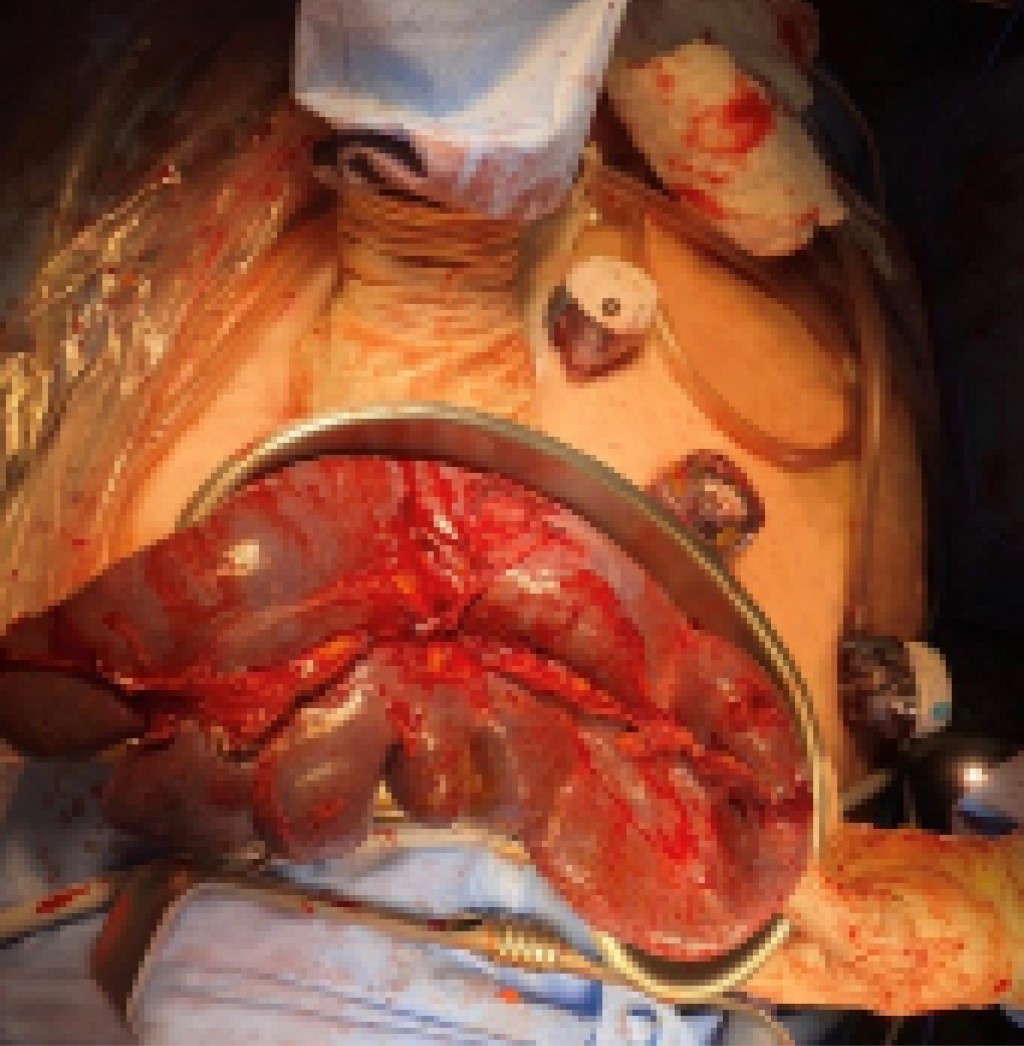

Durante sus primeras horas de estancia intrahospitalaria presentó odinofagia, faringe hiperémica y tos seca, con reporte (+) para virus de Epstein-Barr (VEB). Se solicitó tomografía axial computarizada (TAC) simple de abdomen (Figura 1) reportando derrame pleural bilateral de predominio derecho, esplenomegalia (diámetro máximo de hasta 24 cm), esteatosis hepática con bordes nodulares en su región inferior, presencia de proceso inflamatorio en grasa mesentérica a nivel de mesogastrio con líquido libre en correderas parietocólicas, y en ambas fosas iliacas.

Al introducir el video-laparoscopio se encontró hemoperitoneo de tres litros aproximadamente, esplenomegalia y ruptura de la cápsula, aspecto moteado y sangrado activo (Figura 2); el hígado se observó con apariencia cirrótica y datos de hipertensión portal con sistema venoso colateral umbilical. Ante los hallazgos y la obesidad del paciente, por el espacio reducido, se hizo incisión de 9 cm en flanco izquierdo para retractor mediano (5-9 cm) para continuar procedimiento mano asistida con levantamiento de bazo y mejor control vascular. Además de bisturí armónico (Figura 3), se usó endograpadora vascular de 45 mm para los vasos esplénicos y vasos cortos, debido a su grosor. Se dejaron hemostáticos en lecho esplénico, se visualizó sangrado hepático en capa, y a causa de las condiciones hemodinámicas y de coagulopatía de consumo, se decidió empaquetamiento hepático con compresas introducidas a través de puerto mano asistida, se colocaron dos superiores al hígado y una inferior. Se colocó drenaje cerrado subfrénico izquierdo, se finalizó evento quirúrgico, trasladando al paciente a la unidad de cuidados intensivos (UCI), la pieza midió 24 cm (Figura 4). Durante las primeras horas posquirúrgicas disminuyó gasto hemático por drenaje y mejoró estabilidad hemodinámica.

Figura 1

Figura 4